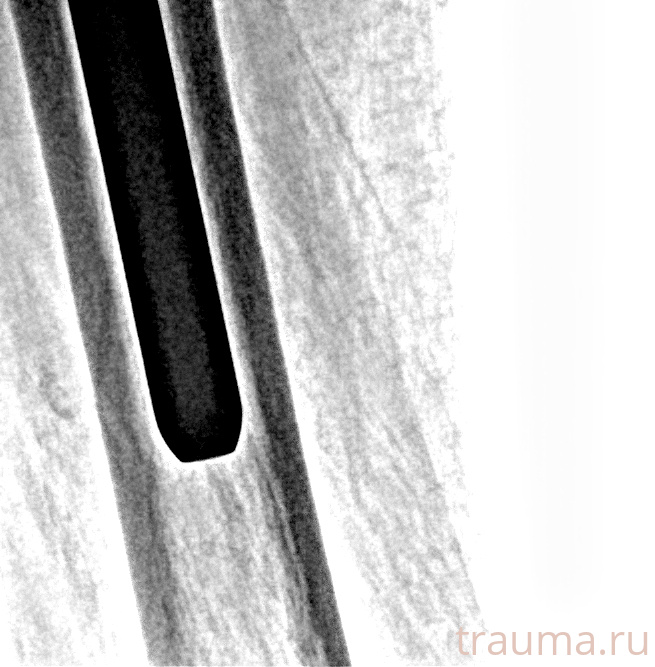

Рентгенограммы

Рентген на дому: по вашему адресу приезжает врач-рентгенолог, травматолог-ортопед с мобильным рентгеновским аппаратом, проводит диагностику травмы или заболевания, делает необходимые рентгенограммы, дает рекомендации по дальнейшему лечению. Получить качественные снимки в домашних условиях возможно благодаря уникальной методике, разработанной МосРентген Центром для института  Склифосовского

Яркость: 1   Контраст: 1   Инвертировать: 0 Увеличение: 1

Перетаскивайте мышь вверх/вниз для контраста, влево/право для яркости. Прокрутка колесом изменяет масштаб. Нажмите Сбросить для возврата к исходному изображению. При увеличении держите мышь в той области, которую хотите рассмотреть.